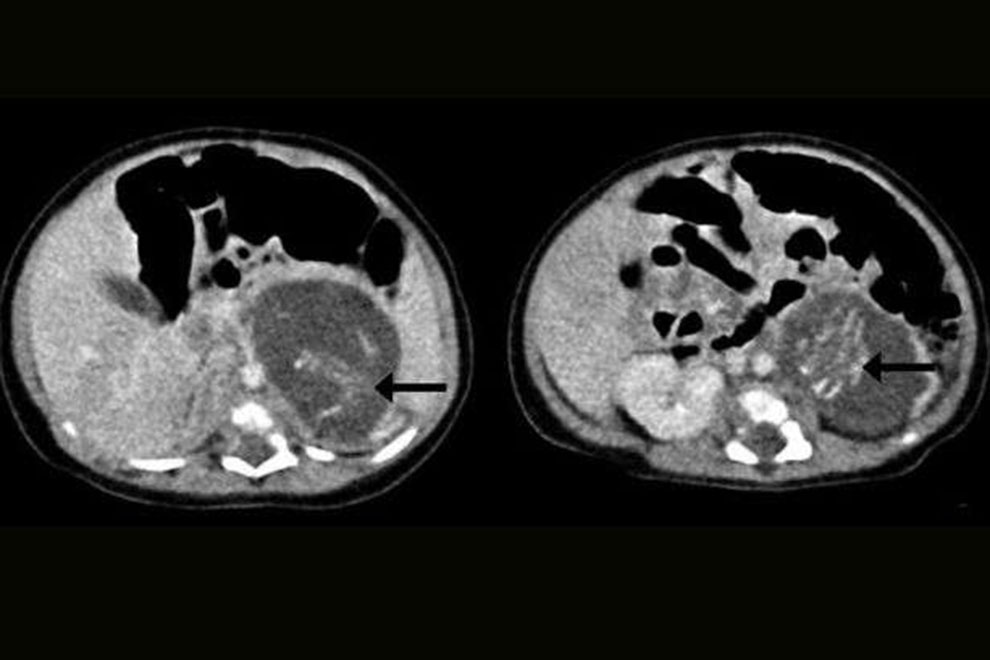

Когда только начались проблемы со здоровьем новорожденной, ее передали доктору Ю Кай-ману, акушеру-гинекологу, работающему в Больнице Королевы Елизаветы в Гонконге, заподозрив наличие опухоли у младенца. Перинатальный ультразвук обнаружил в теле ребенка необычную массу, но врачи не могли понять, что это. Когда девочке было всего 3 недели, была проведена операция, и хирурги обнаружили два плода, находившихся между ее печенью и почками.

Один плод весил 9,3 грамма, другой — 14,2 грамма, что соответствовало примерно 8–10 неделям беременности. Каждый эмбрион был присоединен к плаценте девочки пуповиной.